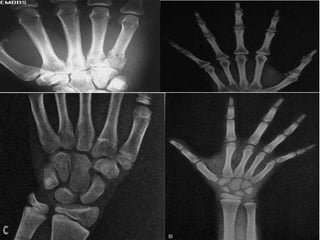

Ossos Curtos Possui equivalência nas três dimensões, ou seja, comprimento x largura x espessura. Ex. ossos do carpo

Ossos Curtos

Ossos Curtos Possuiequivalência nas três dimensões, ou seja, comprimento x largura x espessura. Ex. ossos do carpo